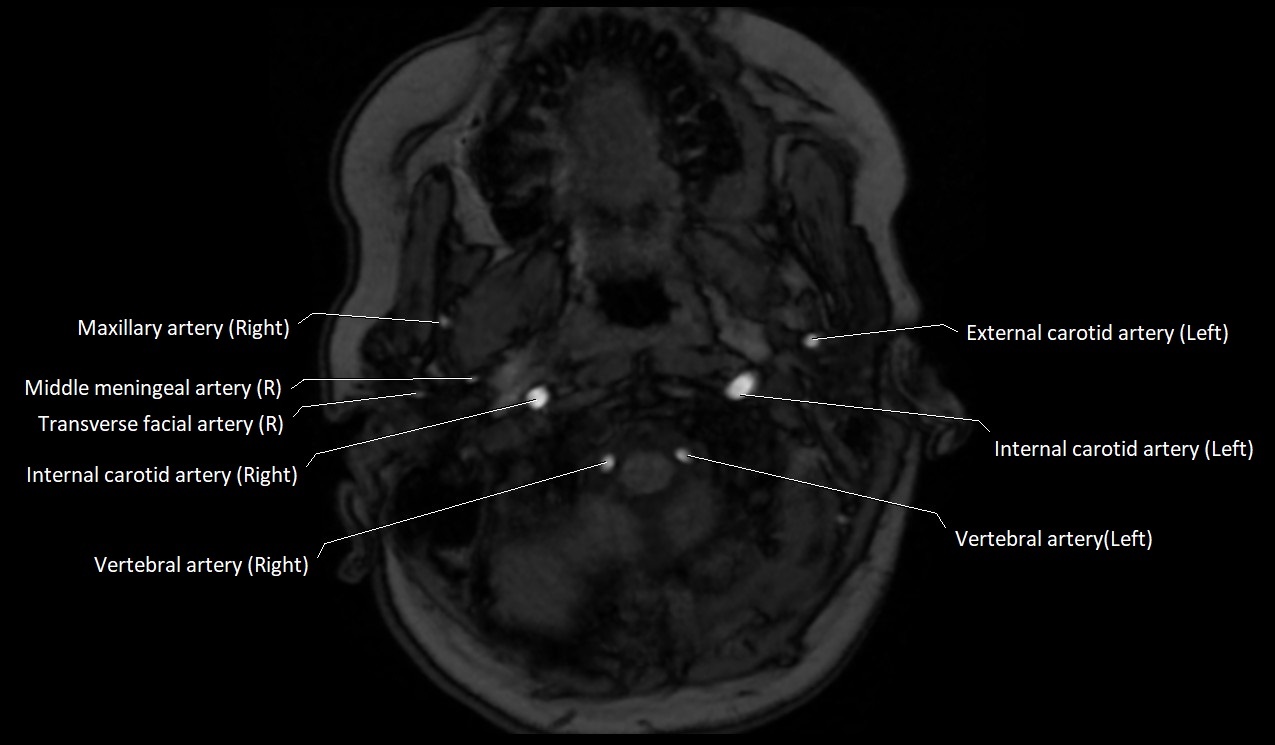

MRI Appearance:

• T1-Weighted Images:

• Appears as a tubular, hypointense (dark) structure relative to muscle

• May show flow void if the blood flow is fast

• T2-Weighted Images:

• Typically hypointense or isointense to muscle, but can be hyperintense if slow flow or stasis is present